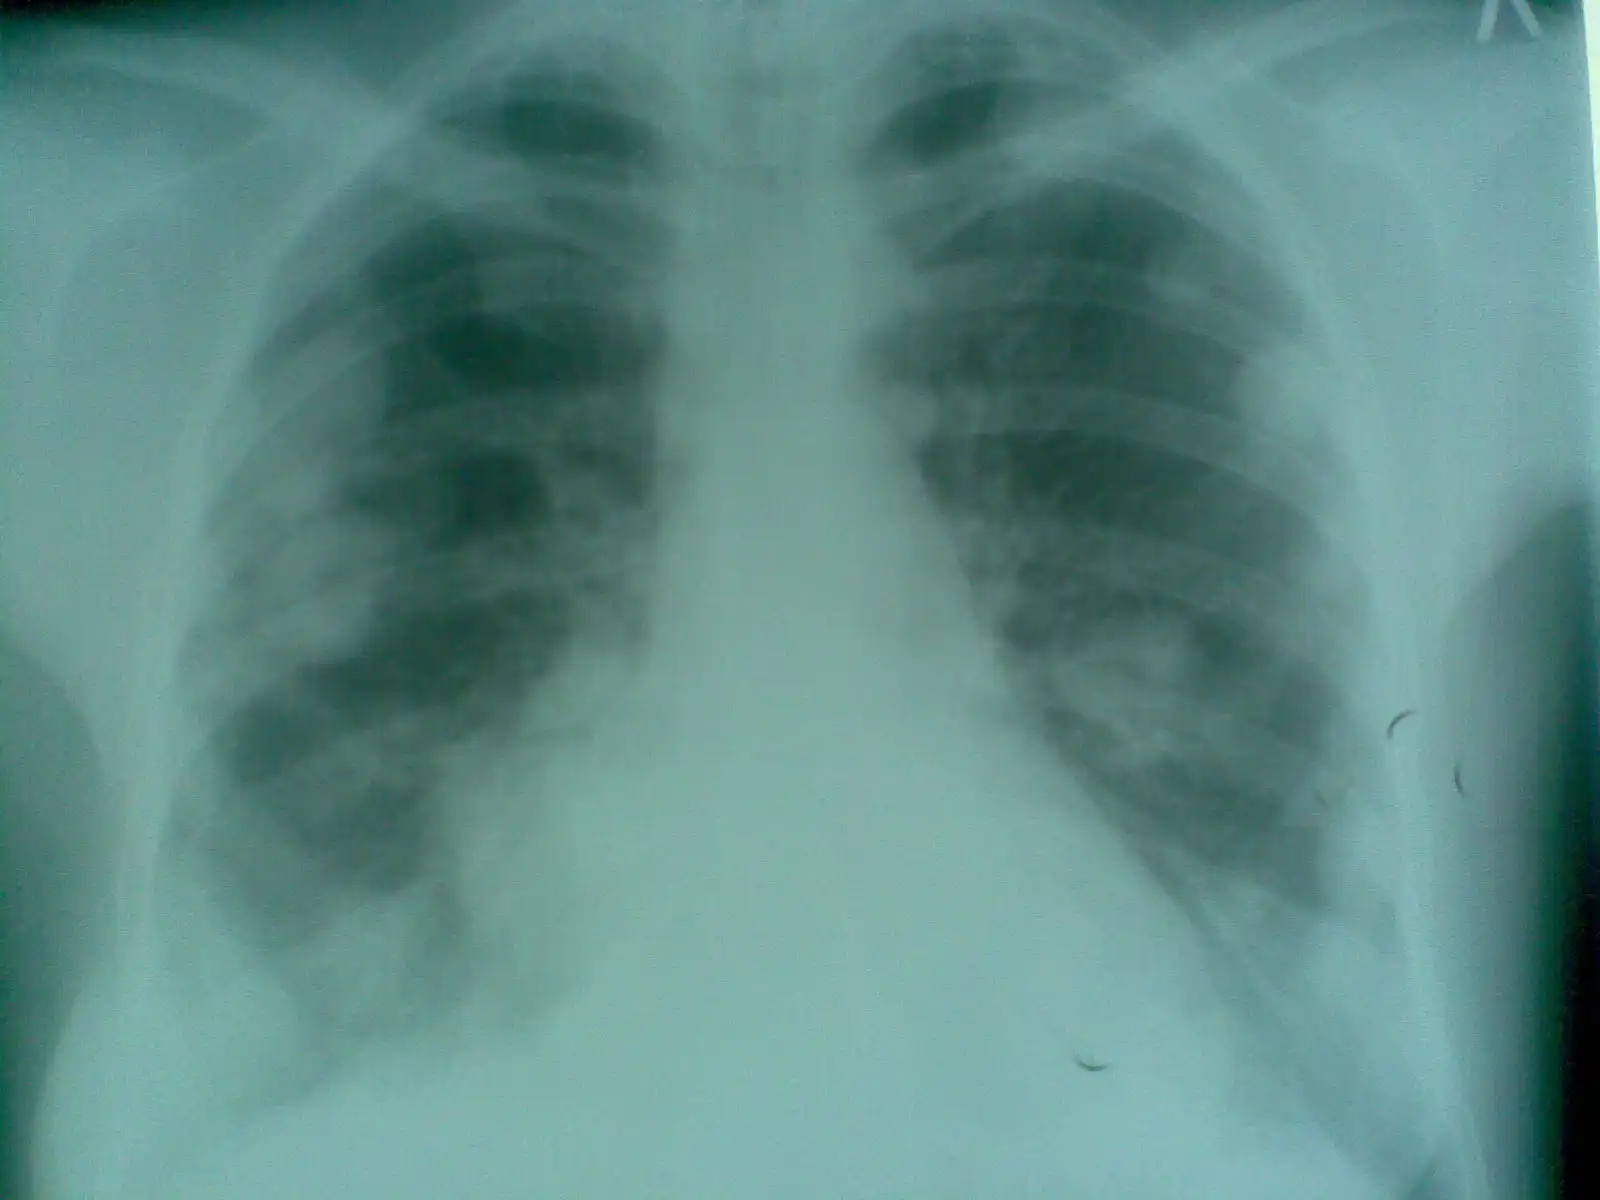

НОРМА: